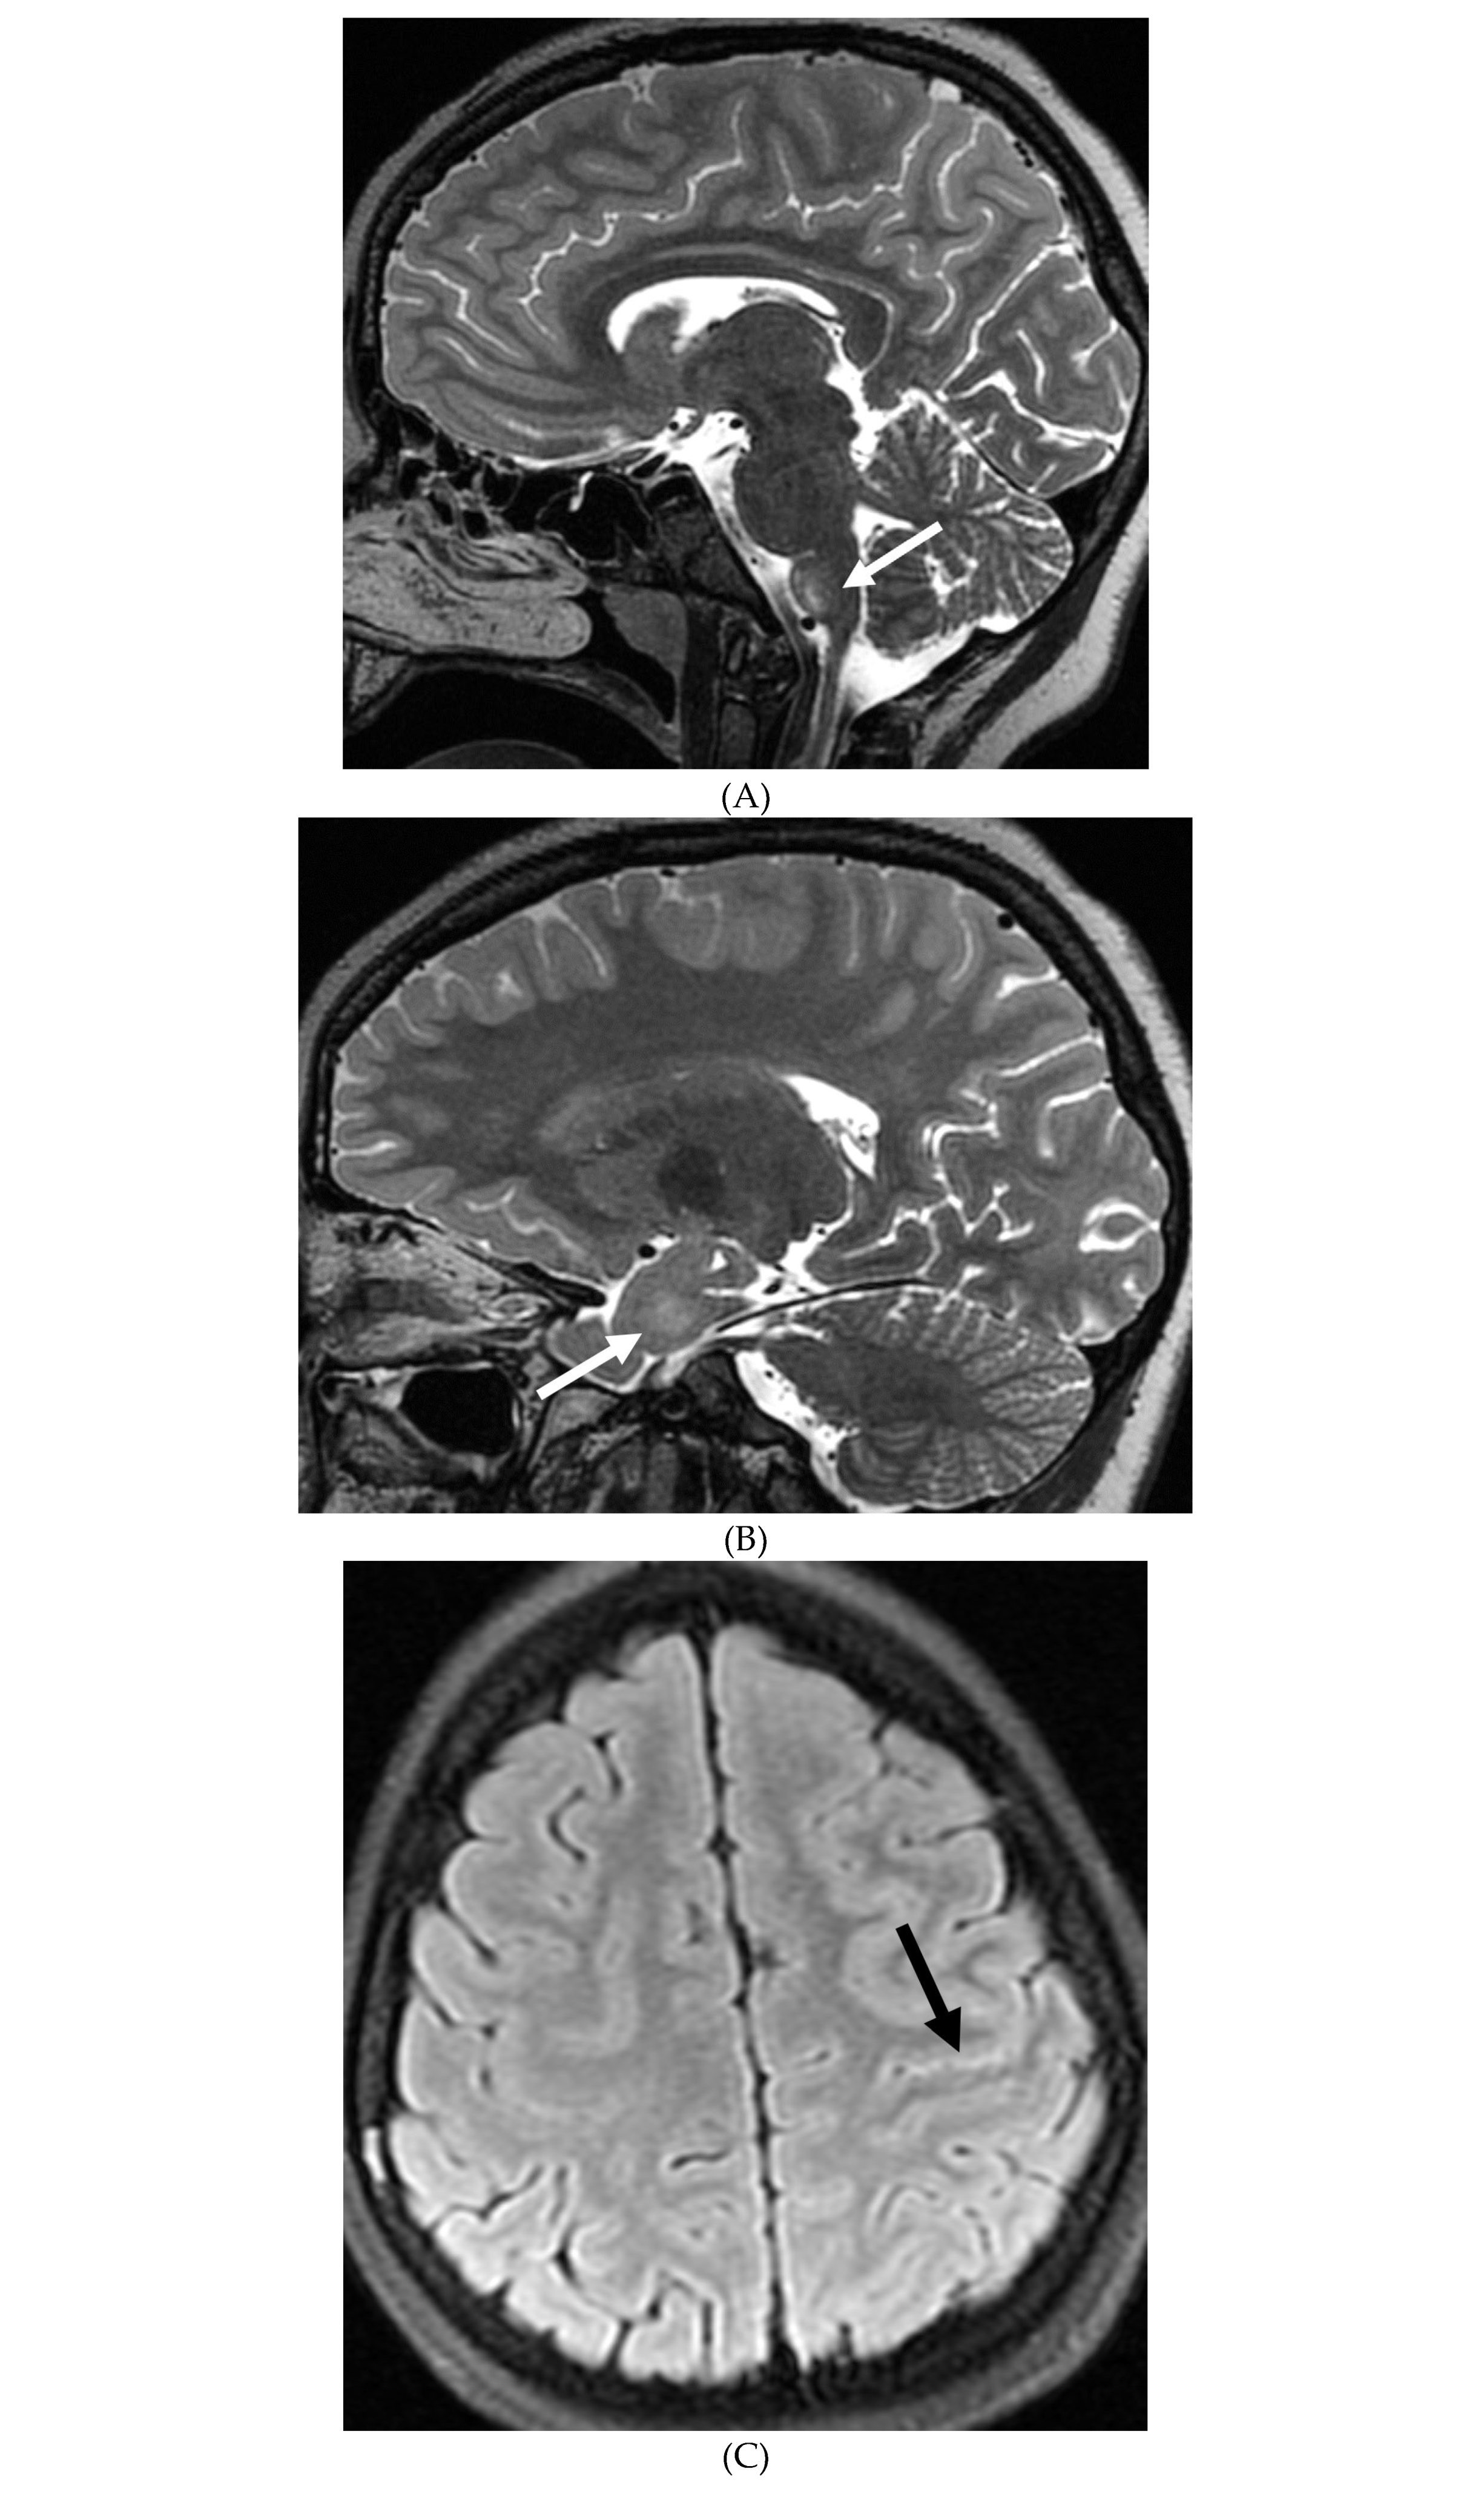

TUBERCULOSIS

- Chiang SS, Khan FA, Milstein MB, Tolman AW, Benedetti A, Starke JR, et al. Treatment outcomes of childhood tuberculous meningitis: a systematic review and meta-analysis. Lancet Infect Dis. (2014) 14:947–57. [CrossRef]

- Dian S, Hermawan R, van Laarhoven A, Immaculata S, Achmad TH, Ruslami R, Anwary F, Soetikno RD, Ganiem AR, van Crevel R. Brain MRI findings in relation to clinical characteristics and outcome of tuberculous meningitis. PLoS One. 2020 Nov 13;15(11):e0241974. PMID: 33186351; PMCID: PMC7665695. [CrossRef]

- Krishnan N, Renganathan L. Tuberculous meningitis sequelae as basal cisternal calcifications. J Pediatr Neurosci. 2016 Jan-Mar;11(1):86-7. PMID: 27195045; PMCID: PMC4862301. [CrossRef]

- Khatri GD, Krishnan V, Antil N, Saigal G. Magnetic resonance imaging spectrum of intracranial tubercular lesions: one disease, many faces. Pol J Radiol. 2018 Dec 29;83:e524-e535. PMID: 30800191; PMCID: PMC6384409. [CrossRef]

- Bomanji JB, Gupta N, Gulati P, Das CJ. Imaging in tuberculosis. Cold Spring Harb Perspect Med. 2015 Jan 20;5(6):a017814. PMID: 25605754; PMCID: PMC4448708. [CrossRef]